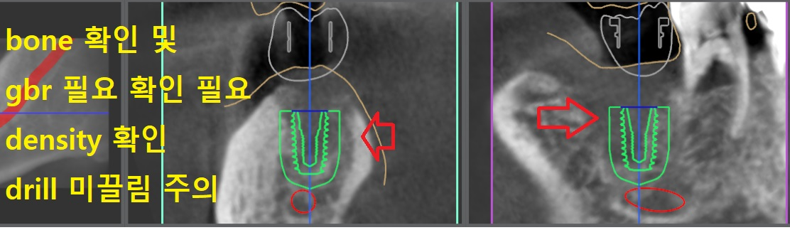

『디지털 임플란트 진단

컴퓨터 사전진단』

당일 바로 디지털 진단을 내렸습니다. 컴퓨터로 임플란트 를 어디에 심어야 좋은 결과를

얻을 수 있는지, 그러면서 주위에 방해 될 수 있는 해부학적 구조물들은 없는지를 살펴봅니다.

이 분의 경우, 이미 bone defect 이 있었던 터라 하치조신경관과 거리가 긴밀합니다.

따라서 gbr 이라는 guided bone regeration 이라는 골유도 재생술을 통해서 사랑니 발치

부위에 심겨질 임플란트 의 식립 위치를 살짝 조정하는 계획을 수립했습니다.